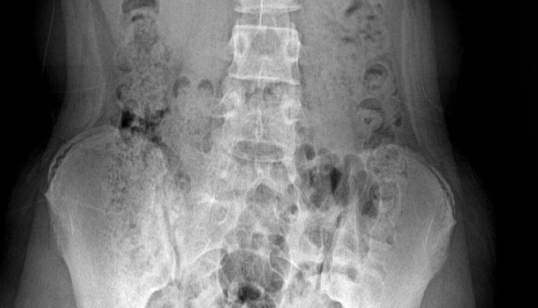

胸腰椎正位片

结构清晰,透视准确